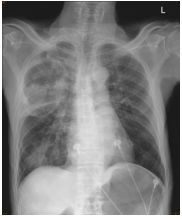

2. A 27-year-old woman had productive cough for one month.